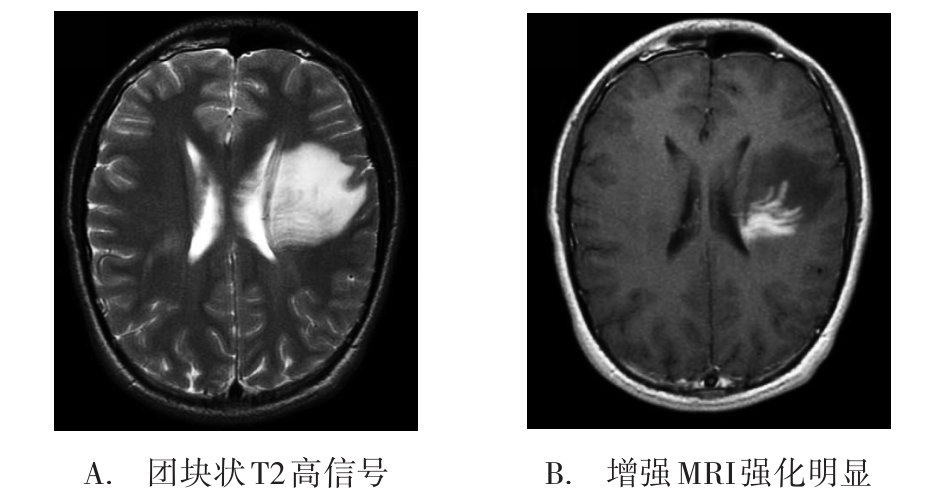

• 肿瘤样脱髓鞘病变报道3例

2023, 48(5):614-617. DOI: 10.13406/j.cnki.cyxb.003183

摘要 (95) HTML (24) PDF 1.29 M (241) 评论 (0) 收藏

摘要: